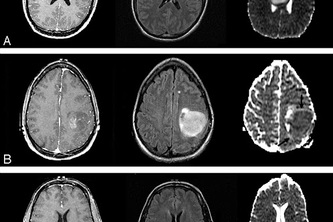

We detect brain tumors with the help of MRI Images.